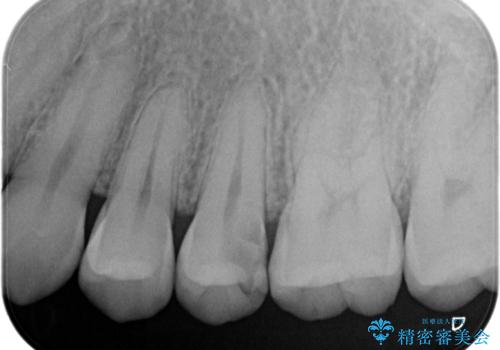

根管治療〜オールセラミッククラウン

- 奥歯がズキズキ痛いことを主訴に来院されました。

根管治療を行なったのち、オールセラミッククラウンにて修復治療を行なっております。

根管治療を行なった歯は速やかに歯冠修復が必要です。